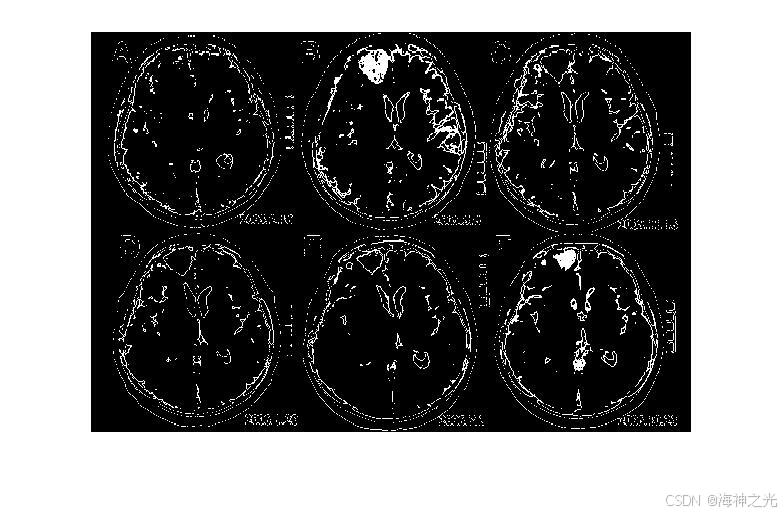

⛄三、运行结果